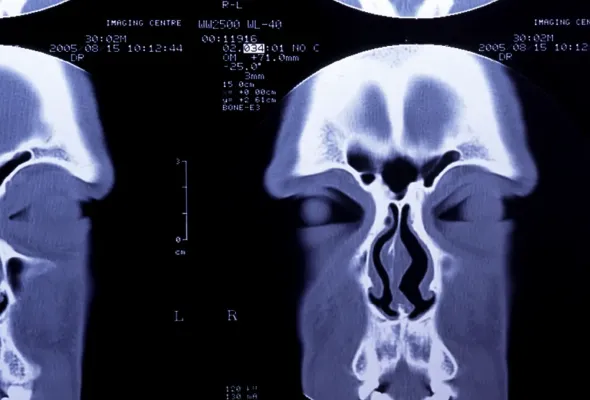

いくら小鼻を小さくしても鼻全体とのバランスや小鼻の皮ふの部分と鼻の穴の形のバランスが崩れれば、決してよい結果になりません。

あまり知られていませんが、鼻翼の手術は鼻の手術の中でもデザイン(理想的な小鼻の作図)の難易度が高い手術です。鼻の穴を美しく見せることはきれいな小鼻にしていく上でとても重要なポイントです。